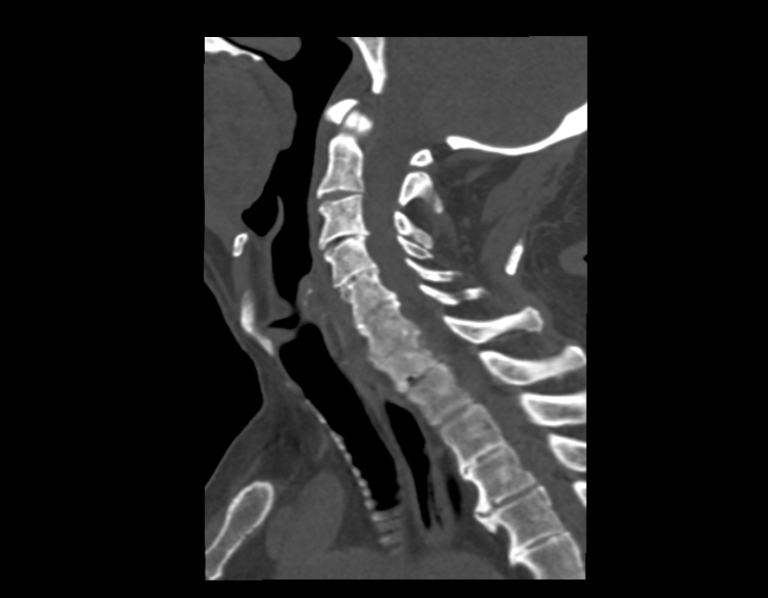

На снимках КТ хорошо визуализируются позвоночные суставы, суставные поверхности, межпозвонковые диски, которые часто подвержены дегенеративно-дистрофическим процессам. На томограммах также можно оценить состояние позвоночного канала, в котором располагается спинной мозг, выявить участки его сужения и предположить степень воздействия на спинномозговые структуры.

При обследовании шейного отдела позвоночника оценивается область основания черепа, семь шейных позвонков, верхние грудные позвонки. Помимо костных структур мультиспиральная КТ показывает состояние близлежащих органов и тканей: трахеи, пищевода, лимфатических узлов, кровеносных сосудов на исследуемом уровне.